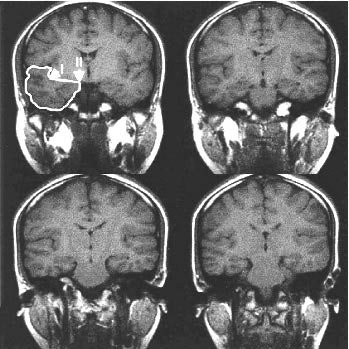

Twenty airline attendants divided into two groups with differing recovery periods were repeatedly subjected to jet lag over five years. The subjects underwent imaging on a 1.5-tesla Signa Horizon scanner (GE Medical Systems, Waukesha, WI). Sagittal T1-weighted images (TR 350 ms; TE 10 ms; slice thickness 5 mm; interslice gap 0 mm) were acquired. The images were then reformatted into 5-mm slices in the coronal plane for the volumetric calculation.

coronal MR images. Volumetric analysis was averaged for each

series of slices per subject. Image courtesy of Nature

Neuroscience.

Using four coronal MRI slices selected between the precentral and postcentral gyri, Cho found evidence that those who had less than five days of recovery time between international flights had smaller right temporal lobe volumes than attendants who had more than 14 days of recovery time, the study stated.